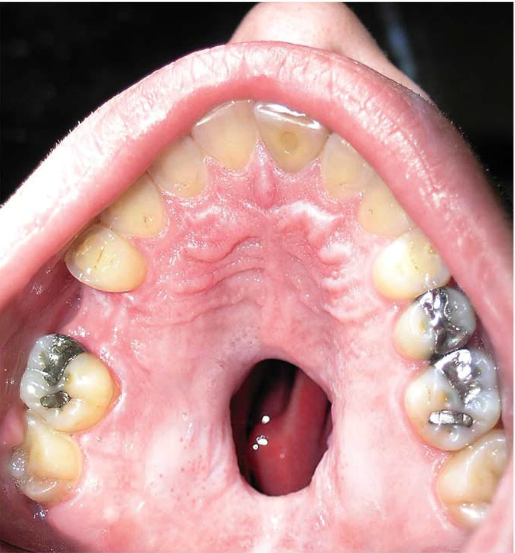

is latest post wasn’t anything to do with the teeth of a patient though. Instead it was a huge palatal perforation due to cocaine abuse, one that stretches the roof of the patient’s mouth.

The photo is a disgusting example of something that is very common in cocaine abusers, to go along with the nasal destruction and sometimes even perforated septum (when two nostrils become one). This patient shows a severe case, but it can sometimes be much less noticeable.

Cocaine restricts the blood vessels throughout the body, especially in the palate, which in turn causes the area to erode due to lack of oxygen. The tissue dies slowly, eventually resulting in a perforation. Many patients don’t seek medical attention right away because of embarrassment or fear that their drug problem will be revealed.

While not immediately life threatening, a perforated palate can lead to many different problems between the two cavities, one of which is simply drinking liquid. Because it can now travel through the opening, some cocaine abusers experience liquid pouring out of their nose.

Even if the drug abuse is stopped, the palate will not regrow and patients require surgery to close the opening. Food and other bacteria, as well as mucus and phlegm, can pass through the hole and cause discomfort and other medical problems in both cavities. Medical attention should be sought as soon as it is noticed.